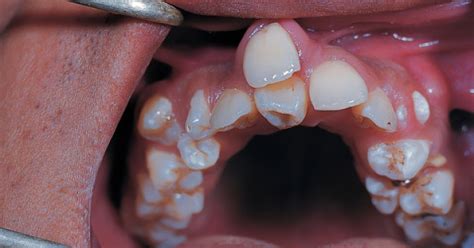

Un diente supernumerario es una pieza dentaria adicional a la formula normal (20 dientes en la dentición temporal y 32 en la permanentes). Los dientes supernumerarios son dientes extra de la dentadura habitual, pero no tienen la forma de diente tal y como la conocemos. Estos dientes pueden presentarse en las diferentes etapas del desarrollo humano, tanto en la dentición temporal como en la mixta y permanente; constituyen uno de los factores que se asocian a la etiología de las maloclusiones y ocasionan alteraciones en la línea media, retención de piezas dentarias, apiñamientos, resorción radicular, diastemas y malformación de otros dientes. Se encuentran en cualquier región del arco y sólo se pueden visualizar radiográficamente.

De entrada, hay que diferenciar entre los supernumerarios, que son dientes en exceso pero no tienen la forma del diente habitual y suelen presentar forma microdóntica, por ejemplo, forma de cono. Los dientes supernumerarios suelen tener una forma muy diversa, diferente a la forma habitual del diente, y suelen sufrir migraciones, es decir, suelen tener direcciones de erupción muy diversas.

- Mesiodens: Éstos se encuentran entre los incisivos centrales superiores, puede ser único, múltiple, unilateral o bilateral, erupcionado o impactado, vertical, horizontal o invertido; suelen presentarse también en la zona mandibular. Los supernumerarios más habituales son el mesiodens, que es un diente que sale entre los incisivos centrales superiores. Dientes supernumerarios mesiodens: se trata de un diente extra que nace en la región de los incisivos centrales superiores o un diente que sale en el paladar. Puede nacer solo o con un compañero y, por lo general, tiene forma de cono.